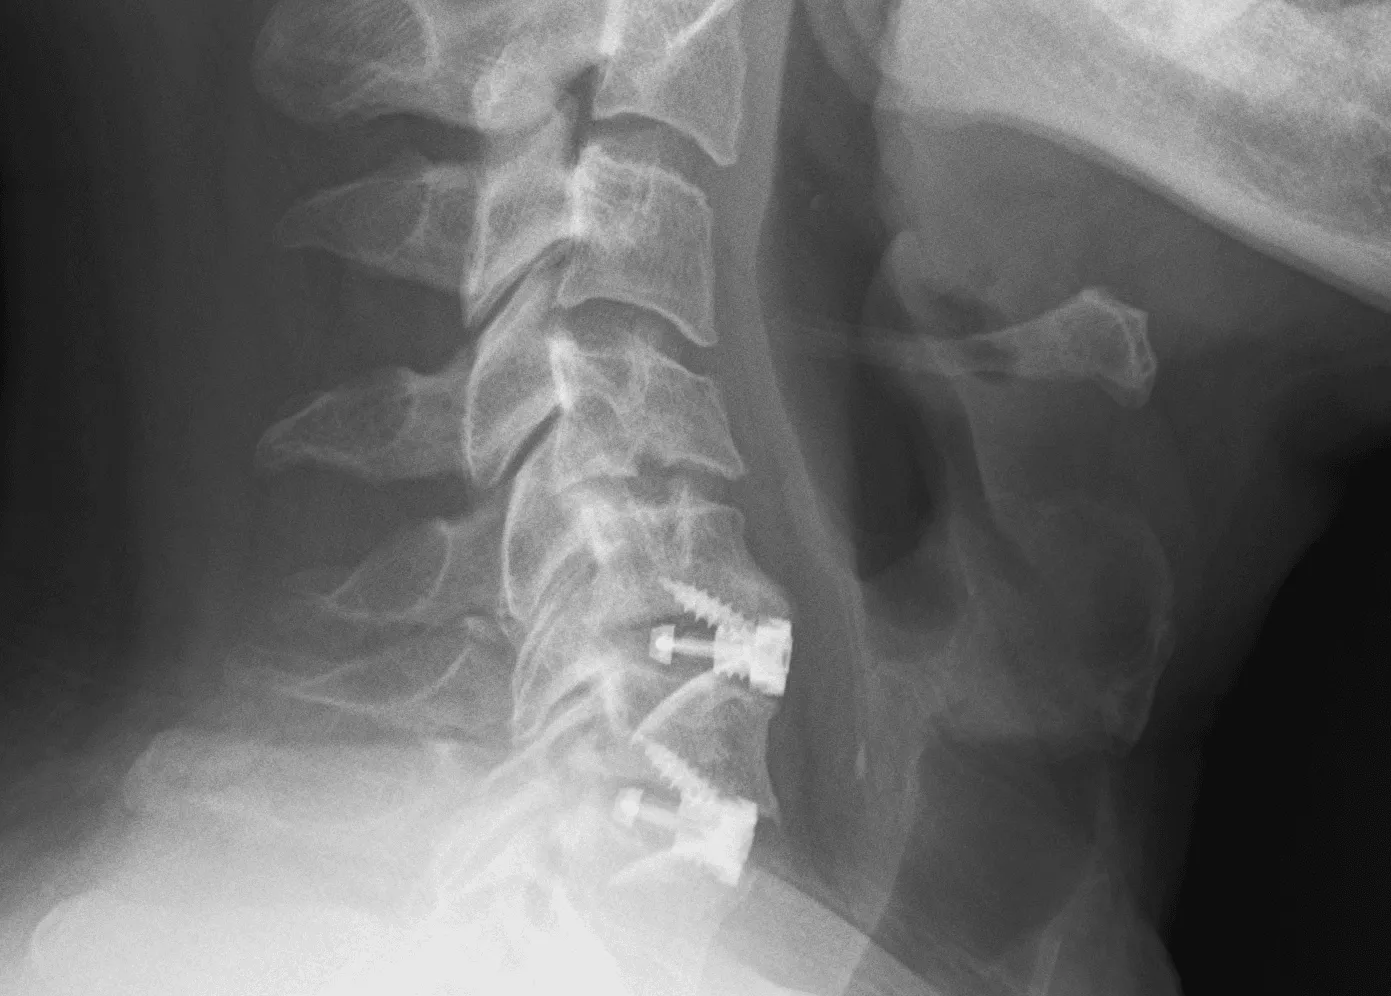

X-Ray

An X-ray provides rapid images of the bony structures of the cervical spine. It can reveal narrowed disc spaces, fractures, bone spurs, and changes consistent with osteoarthritis. X-rays do not show soft tissue structures like discs or nerves.

Xray image of a neck with a metal cage placed during ACDF surgery.

Traditional Fusion Surgery (ACDF)

Anterior cervical discectomy and fusion (ACDF) has been the standard surgical treatment for cervical disc herniation for decades. The procedure involves removing the damaged disc, relieving pressure on the affected nerve or spinal cord, and then permanently fusing the adjacent vertebrae using bone graft and metal hardware. While effective for many patients, fusion permanently limits the neck’s natural range of motion and transfers mechanical stress to adjacent spinal levels. Research has shown that adjacent segment disease requiring reoperation affects approximately 11% of fusion patients, and radiographic degeneration at adjacent levels develops in up to 30%.

An xray highlighting the ACDF on the Cervical spine.